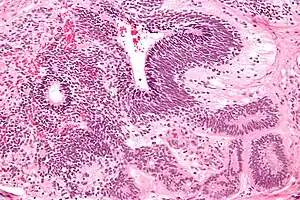

Dysgerminomas are comparable to testicular seminomas and account for approximately 32- 37% of all OGCTs.[1] They are particularly prominent in individuals with dysgenic gonads of 46, XY pure gonadal dysgenesis patients.[1] Based on gross examinations, dysgerminomas are characterized by having a 'solid, lobulated, tan, flesh-like gross appearance with a smooth surface'.[1] Microscopically, the cellular structure is distinguished by a round-ovoid shape containing ample eosinophilic cytoplasm and an irregularly shaped nuclei.[1] The uniformly positioned cells are separated through the fibrous strands and lymphocytic infiltration is commonly observed.[4]